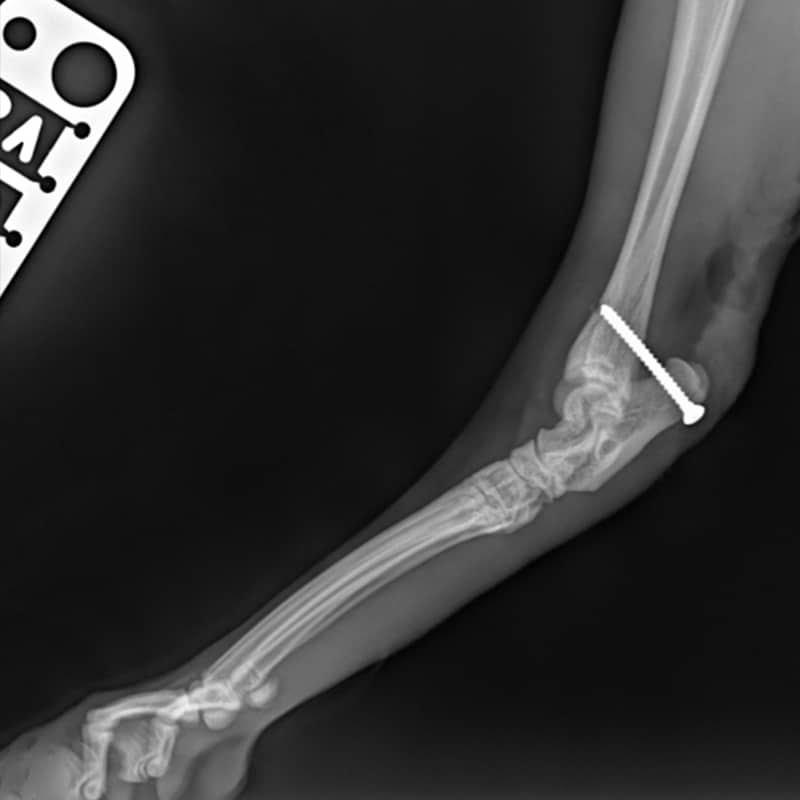

Fracture Repair

We are equipped and skilled to be able to choose the best methods to fix broken bones, including Plates and Screws, External Fixators, Pins and Wires.